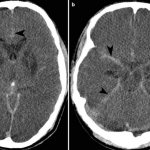

Dementia of the vascular type is diagnosed in the presence of clinical data, characteristic anamnestic or neuroimaging signs of cerebrovascular disease: previous stroke or cases of subclinical local cerebral ischemia.

It is also important to have a cause-and-effect relationship and a relationship in time between brain damage of vascular etiology and the development of cognitive impairment. The very presence of dyscirculatory disorders according to neuroimaging, as well as the presence of neurological disorders - hemiparesis, speech and swallowing disorders, walking and urination disorders, are mandatory.

In addition to a thorough neurological examination and targeted laboratory tests, MRI or MSCT is necessary to identify infarcts and white matter lesions.

In most patients at the third stage of alcoholism, when the personality has degraded, atrophic changes in the brain are noticeable, in the form of dilated cerebral ventricles and furrows in the cerebral cortex.